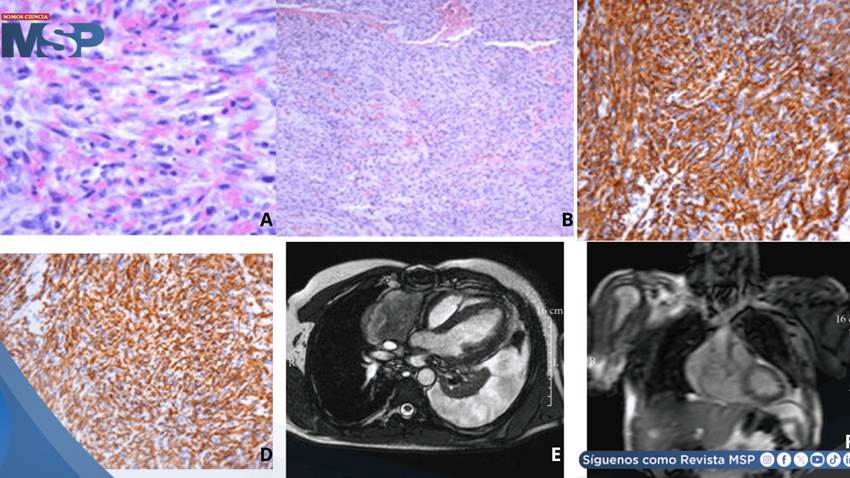

El estudio histopatológico confirmó el diagnóstico de angiosarcoma moderadamente diferenciado. La neoplasia mostraba una arquitectura heterogénea, con áreas de alta y baja celularidad, presencia de estroma colagénico denso y zonas mixoides.

En algunas regiones se observaban estructuras vasculares irregulares revestidas por células tumorales atípicas, mientras que en otras predominaban espacios vasculares más amplios y desorganizados.

El análisis inmunohistoquímico fue determinante, evidenciando positividad para marcadores endoteliales como CD31, CD34 y factor Von Willebrand, además de un índice proliferativo elevado cercano al 60%, lo que confirmaba la naturaleza agresiva del tumor.

Tras la cirugía, el paciente fue trasladado a medicina interna en condiciones hemodinámicas estables. Estudios posteriores, incluyendo resonancia magnética cardíaca, revelaron una masa de gran tamaño que se extendía desde la aurícula derecha hacia el mediastino, comprometiendo estructuras vasculares cercanas. A pesar de la extensión local, los estudios iniciales no evidenciaron metástasis a distancia.